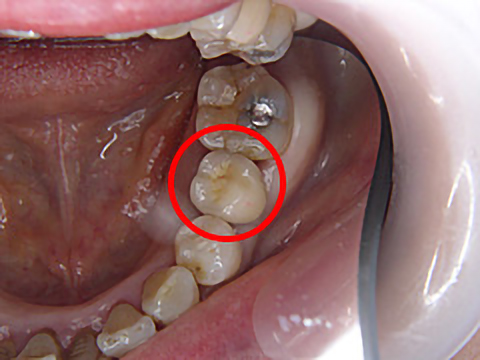

虫歯で歯が根の部分から割れてしまったため、インプラント治療を行いました。 インプラントで治療した歯(治療後画像 :〇 )と十数年前に他院にて治療したメタルボンドの歯とで、隣り合った箇所の見た目が違うため、メタルボンドの再治療を検討されています。